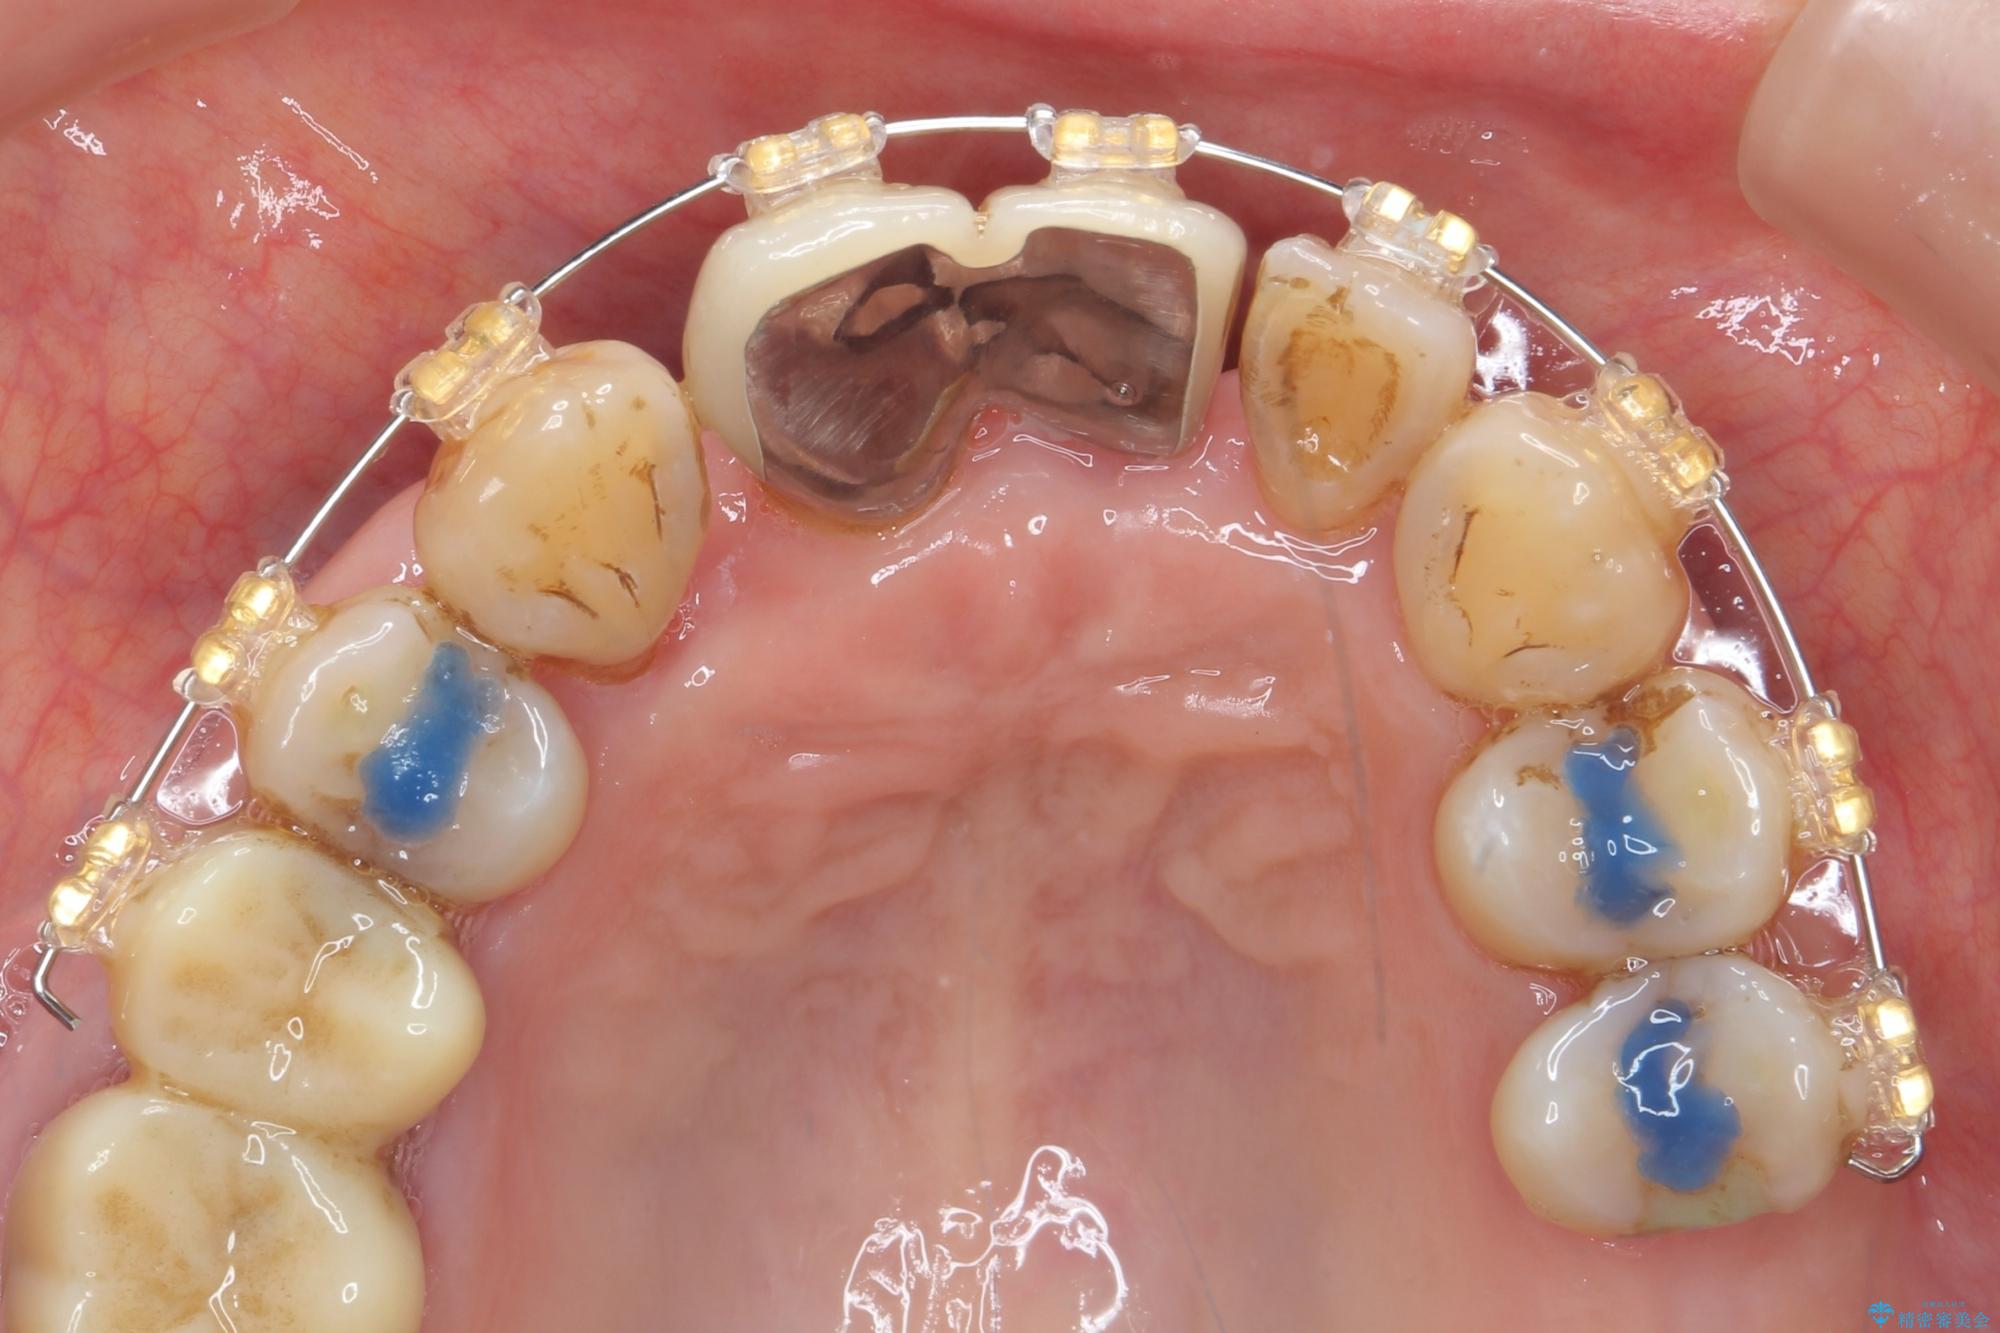

治療中

歯の総合的なマネージメントを行う包括的歯科治療の実践[ 歯周病・矯正・セラミック補綴 ] 治療中画像 歯の総合的なマネージメントを行う包括的歯科治療の実践[ 歯周病・矯正・セラミック補綴 ] 治療中画像 歯の総合的なマネージメントを行う包括的歯科治療の実践[ 歯周病・矯正・セラミック補綴 ] 治療中画像 歯の総合的なマネージメントを行う包括的歯科治療の実践[ 歯周病・矯正・セラミック補綴 ] 治療中画像 歯の総合的なマネージメントを行う包括的歯科治療の実践[ 歯周病・矯正・セラミック補綴 ] 治療中画像 歯の総合的なマネージメントを行う包括的歯科治療の実践[ 歯周病・矯正・セラミック補綴 ] 治療中画像 歯の総合的なマネージメントを行う包括的歯科治療の実践[ 歯周病・矯正・セラミック補綴 ] 治療中画像 歯の総合的なマネージメントを行う包括的歯科治療の実践[ 歯周病・矯正・セラミック補綴 ] 治療中画像 歯の総合的なマネージメントを行う包括的歯科治療の実践[ 歯周病・矯正・セラミック補綴 ] 治療中画像 歯の総合的なマネージメントを行う包括的歯科治療の実践[ 歯周病・矯正・セラミック補綴 ] 治療中画像 歯の総合的なマネージメントを行う包括的歯科治療の実践[ 歯周病・矯正・セラミック補綴 ] 治療中画像